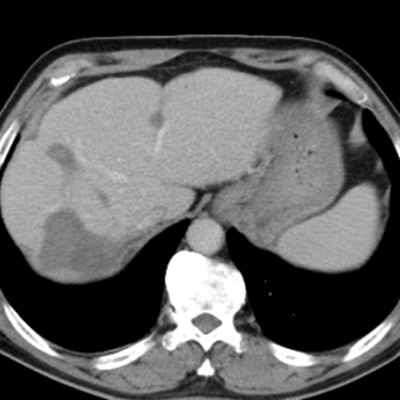

治療后:未見(jiàn)明顯活性轉(zhuǎn)移腫瘤

隨后,根據(jù)基因檢測(cè)結(jié)果制定了化療+靶向治療方案。經(jīng)過(guò)精準(zhǔn)治療,劉大爺?shù)牟≡畲笮⊙杆倏s小,病灶數(shù)量不斷減少,影像學(xué)評(píng)估已經(jīng)看不見(jiàn)之前那些小的病灶了。

經(jīng)過(guò)兩次肝臟轉(zhuǎn)移瘤射頻消融手術(shù),一次腸癌根治手術(shù)聯(lián)合腹腔轉(zhuǎn)移腫瘤切除手術(shù),劉大爺體內(nèi)的大腫瘤完全消除,僅有幾處沒(méi)有明確活性的小病灶。